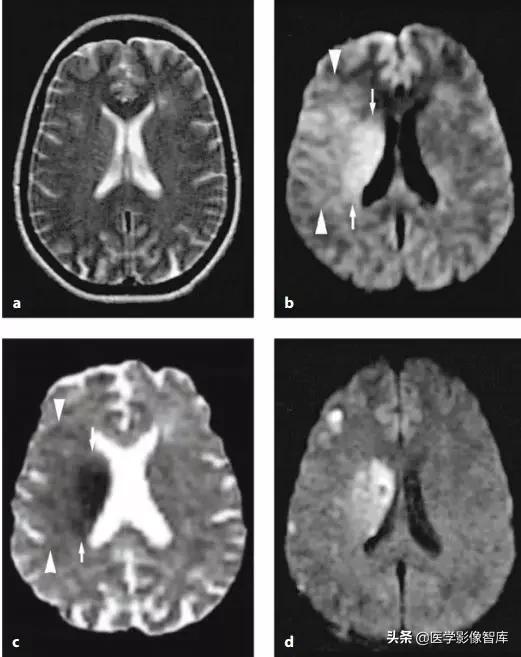

克雅病(CJD,Creutzfeldt–Jakob disease)是由朊蛋白病毒所致的一类具有传染性、进行性恶化的神经系统变性疾病,主要表现为进行性痴呆、精神障碍、肌阵挛等。病程后期脑电图可见特异性的三相波,部分患者脑脊液 14-3-3 蛋白阳性。此种病目前为止没有任何有效的治疗方式,患者在出现临床症状后一般在半年至两年内死亡。CJD 早期无影像异常,中晚期常出现一些影像异常,比较典型的有花边征(cortical ribbon,又叫飘带征,特点即为皮质 DWI 高信号,常见于散发型 CJD),曲棍球征(hockey-stick sign,指双侧丘脑枕和背内侧丘脑同时对称性受累的 T2、DWI 高信号病变,常见于变异性 CJD)。临床上,进行性痴呆、椎体 / 椎体外系症状、脑电图异常(三相波)患者若出现花边征,常常指向 CJD。图 3 显示一个散发型 CJD 患者磁共振检查结果。

图 3 花边征(飘带征),散发型 CJD 患者,A、B 为 DWI,C 为 ADC 图,D 为 FLAIR。可见患者双侧皮层不对称的 DWI 高信号(箭头),基底节区 DWI 高信号(三角箭头),病灶 ADC 图上为低信号,FLAIR 上高信号